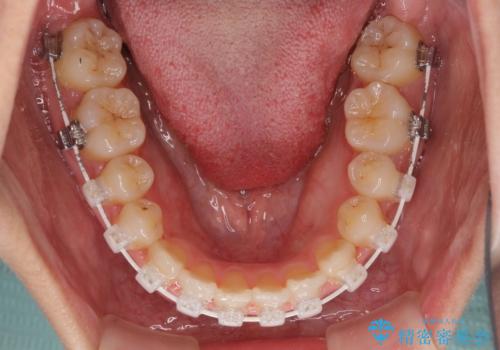

前歯のクロスバイトと変色した歯 ワイヤー矯正とセラミック治療

- 前歯のクロスバイトと神経を取り除いた後に変色してしまった前歯を気にして来院された患者様です。

ワイヤー矯正により矯正治療を行った後に、前歯の補綴治療を行うこととしました。

インビザラインでの矯正治療も十分に対応可能でしたが、自己管理の煩わしさから、ワイヤー矯正を行うこととしました。